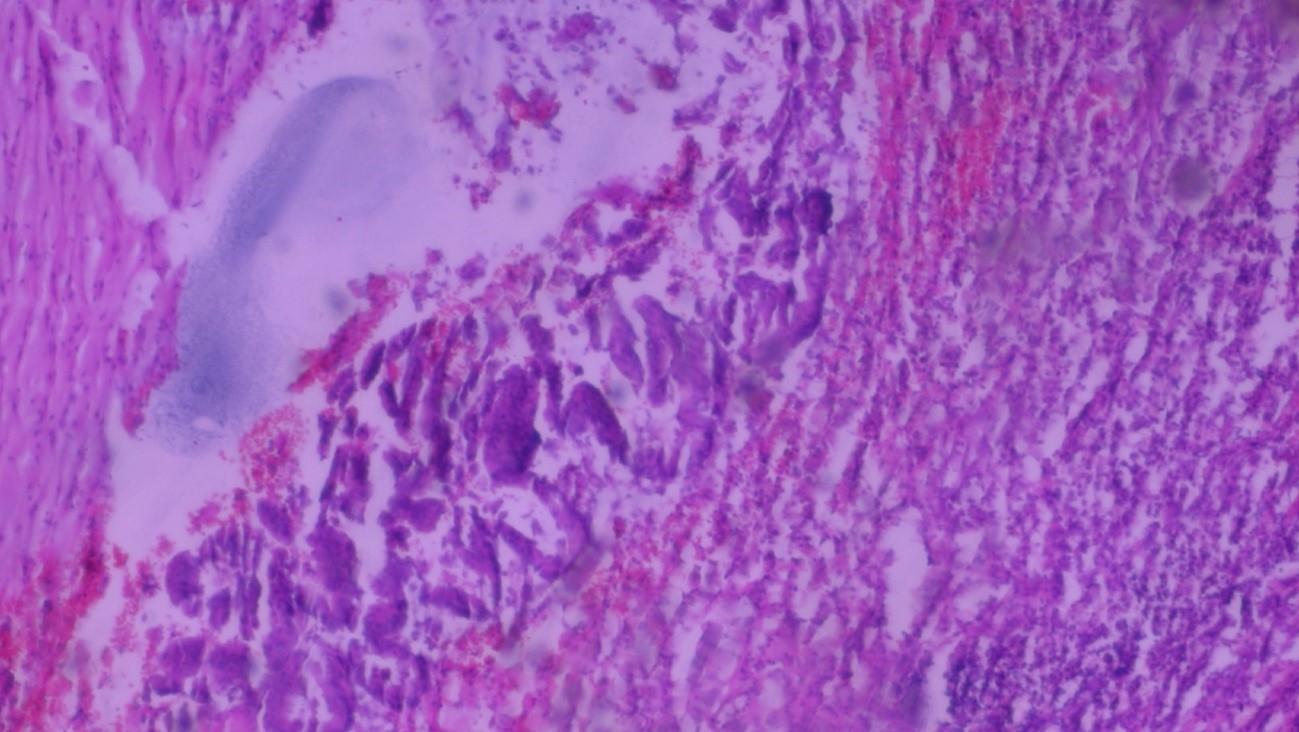

Volver a los detalles del artículo Diagnóstico incidental de tumor de apéndice cecal